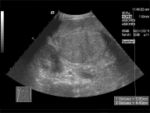

Bild 2. Sonographie des Abdomens bei Leberzirrhose mit nodulärer Formation (Transversalschnitt).

Im Ultraschall stellt sich die Leber inhomogen dar. Der Leberrand ist wellig, die Binnengefässe sind rarefiziert. Der Lobus caudatus kann vergrössert sein. Sehr gut können mit dem Ultraschall ein Aszites und eine Milzvergrösserung (Splenomegalie) erkannt werden. Mit der Farbduplexsonographie lässt sich in den Lebervenen eine verminderte Elastizität der Leber, in der Pfortader ein verminderter Fluss sowie in der Leberarterie ein erhöhter peripherer Widerstand messen. Mit Sonar ist nicht immer eine definitive Diagnose möglich.